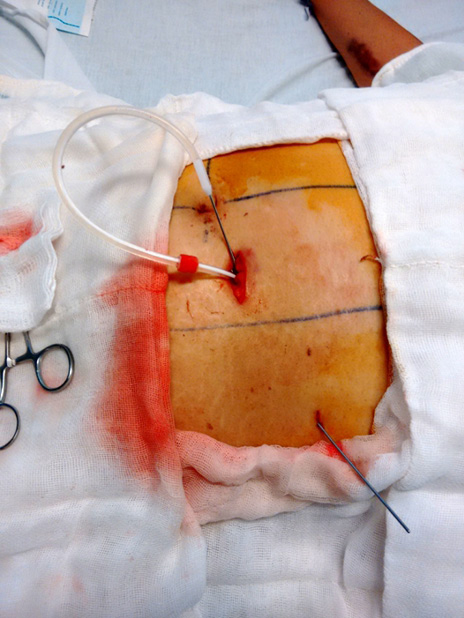

El sitio de colocación deberá ser evaluado previamente, en los pacientes en que esto sea posible, en bipedestación y vestido para marcar la línea del cinturón. En aquellos que no es posible lo anterior, deberá considerarse un sitio aproximado -evitando los pliegues naturales- si tiene un abundante depósito de panículo adiposo deberá considerarse su caída y movimiento por la gravedad. El sitio ideal para los autores es para-medio izquierdo unos 2 cm debajo de la cicatriz umbilical, sin embargo podrán considerarse otras posiciones dependiendo de la anatomía de los pacientes (ej., supraumbilical) (figura 1).

Figura 1. Se marcan los bordes de los rectos abdominales y la cicatriz umbilical para determinar el mejor sitio de colocación. Fuente: archivo clínico electrónico.